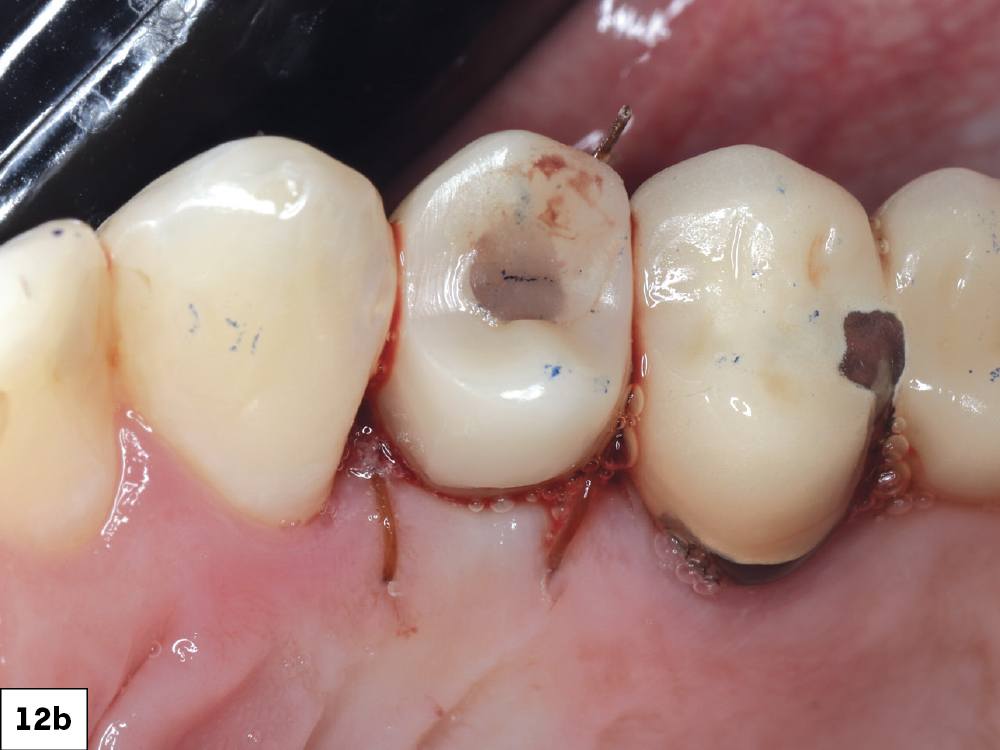

Each screw-retained crown was seated onto the corresponding Glidewell HT Implant, torqued to the manufacturer’s specifications, and sealed with PTFE tape and composite resin

Figures 12a, 12b: Each screw-retained crown was seated onto the corresponding Glidewell HT Implant, torqued to the manufacturer’s specifications, and sealed with PTFE tape and composite resin. Occlusal contacts required only minor adjustments. Occlusion was relieved in the design phase to promote undisturbed osseointegration and eliminate premature loading. The fit was passive, the emergence contours harmonious, and the esthetic integration excellent.